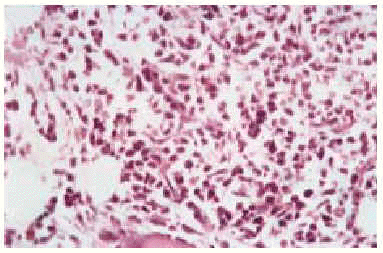

El estudio histológico de las lesiones, tanto de los nódulos como de las maculopápulas, ponía de manifiesto la existencia, bajo una epidermis normal, de un denso infiltrado que ocupaba desde dermis media hasta hipodermis respetando una fina banda superficial (fig. 3). El infiltrado era monomorfo y estaba formado por células de citoplasma escaso y núcleos irregulares con abundantes mitosis (fig. 4). En el estudio inmunohistoquímico se evidenciaba que dichas células pertenecían a la serie monocito-histiocitaria (CD43+, CD68+, CD15+) (fig. 5), con índice proliferativo muy alto (fig. 6).

Fig. 3.--Tinción con hematoxilina-eosina. Epidermis sin alteraciones. Denso infiltrado desde dermis media, respetando una banda superficial.

Fig. 4.--Detalle de las células del infiltrado.